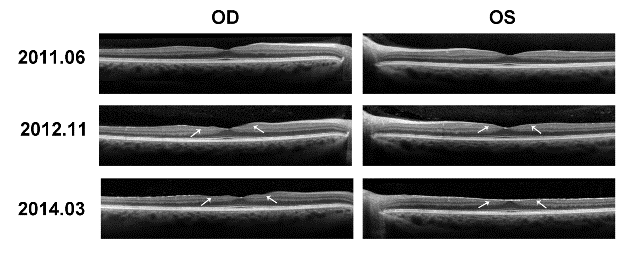

| Figure 1: Optical Coherence Tomography (OCT). Images are labeled according to the date taken; each date corresponds to one set of left and right eye images. 2011.06 and 2012.11 depict normal retinal layers throughout. The left and right eye images taken 2014.03 are notable for left eye greater than right eye thinning of the retinal nerve fiber layer, ganglion cell layer, inner plexiform and inner nuclear layers with loss of the foveal pit in the left eye. |